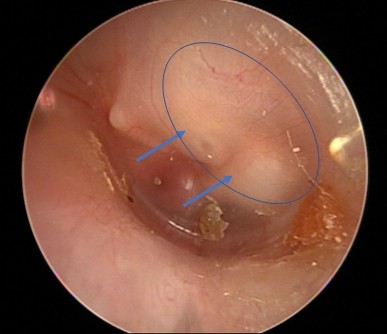

| ▲ 진주종 3기 내시경 사진 [한림대동탄성심병원 제공] |

가장 보편화된 치료법은 현미경을 이용해 진주종을 제거하는 방법이다. 최근에는 귀수술에 내시경이 도입되면서, 귀의 외부절개 없이 귓구멍을 이용해 병변에 접근할 수 있고, 내시경에서 제공하는 넓은 시야로 정확하고 빠르게 진주종을 제거할 수 있게 됐다. 특히 진주종을 완벽히 제거하지 못할 경우 진주종이 다시 자라게 돼 재수술을 받아야 한다. 재수술 시에는 더 넓은 시야를 확보해야 하기 때문에 귀 뒤를 절개할 가능성이 높아져 수술법을 잘 택하는 것이 중요하다.

후천성과 달리 유소아에서 발견되는 선천성 진주종은 귀에서 진물이나 통증 등의 증상이 없고, 일측성으로 난청이 발생하더라도 소아가 난청 증상을 자각하고 표현하기가 어려워 가정에서 알아차리기는 쉽지 않다. 따라서 소아가 감기나 중이염 등으로 병원을 방문하게 될 경우 귓속검사를 할 때 혹시라도 진주종이 있는지 면밀하게 관찰하여 최대한 조기에 발견하는 것이 중요하다.